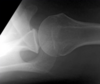

38

what is this

Défaut hill-sachs postéro-supérieur : trace d'une luxation antérieure qui a eu lieu